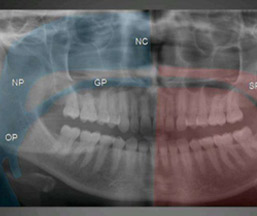

OPG

What is OPG? OPG stands for Orthopantomography. It is a special method for obtaining radiographs of the teeth-bearing jaws, both upper and lower. How is it different from regular X-ray machines? A regular X-ray machine cannot take detailed pictures of